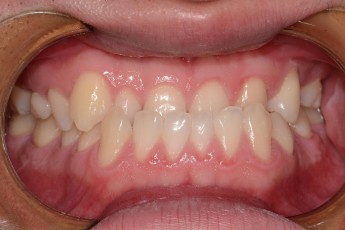

BEFORE & AFTER

- 덧니교정